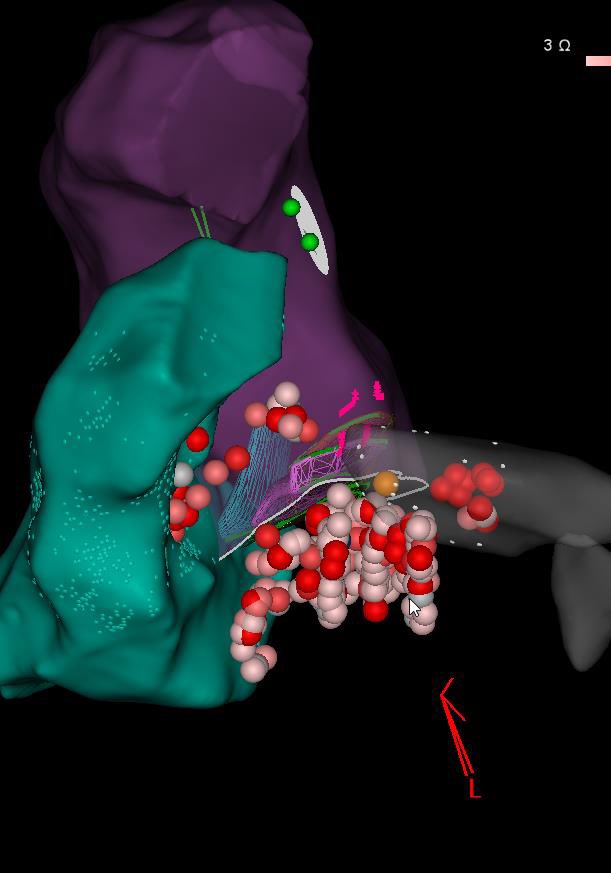

Tapped out on this Summit PVC. Earliest site GCV within 1cm of LM. Ablated from LVOT, RVOT, prox GCV. Half NS, 30W lesions for 3 min endocardial, only got temp suppression. Any other conventional options? Roderick Tung Amin Al-Ahmad, MD Anand Alex Turin AFPanico #EPeeps

A case of the missing 20ms… Despite double ant line, mitral flutter didn’t terminate. Map shows incomplete histogram due to epi bridge. Found endo landing zone laterally on base of appendage #EPeeps AFPanico Alex Turin Gina Glover Roderick Tung Amin Al-Ahmad, MD Anand

Another summit PVC, 23% burden. This time successfully ablated from the LA vestibule. Earliest signal was only ‘on time’, but site was close enough to the epicardium Gina Glover AFPanico Amin Al-Ahmad, MD JMC Roderick Tung Amole Ojo Anand Alex Turin #EPeeps

#Fluoroless transseptal via lower edge of ASD occluder device for redo fib and mitral flutter #EPeeps Amole Ojo Mansour Razminia AFPanico Alex Turin Dana Johnson MD MPH Amin Al-Ahmad, MD JMC Roderick Tung Daniel Alyesh

What’s happening? EP fellows chime in Faisal Merchant Mikhael El-Chami Alex Turin Amole Ojo AFPanico JMC Kalyanam Shivkumar MD PhD Roderick Tung Amin Al-Ahmad, MD Sergio Pinski Gregory Michaud Anand #EPeeps